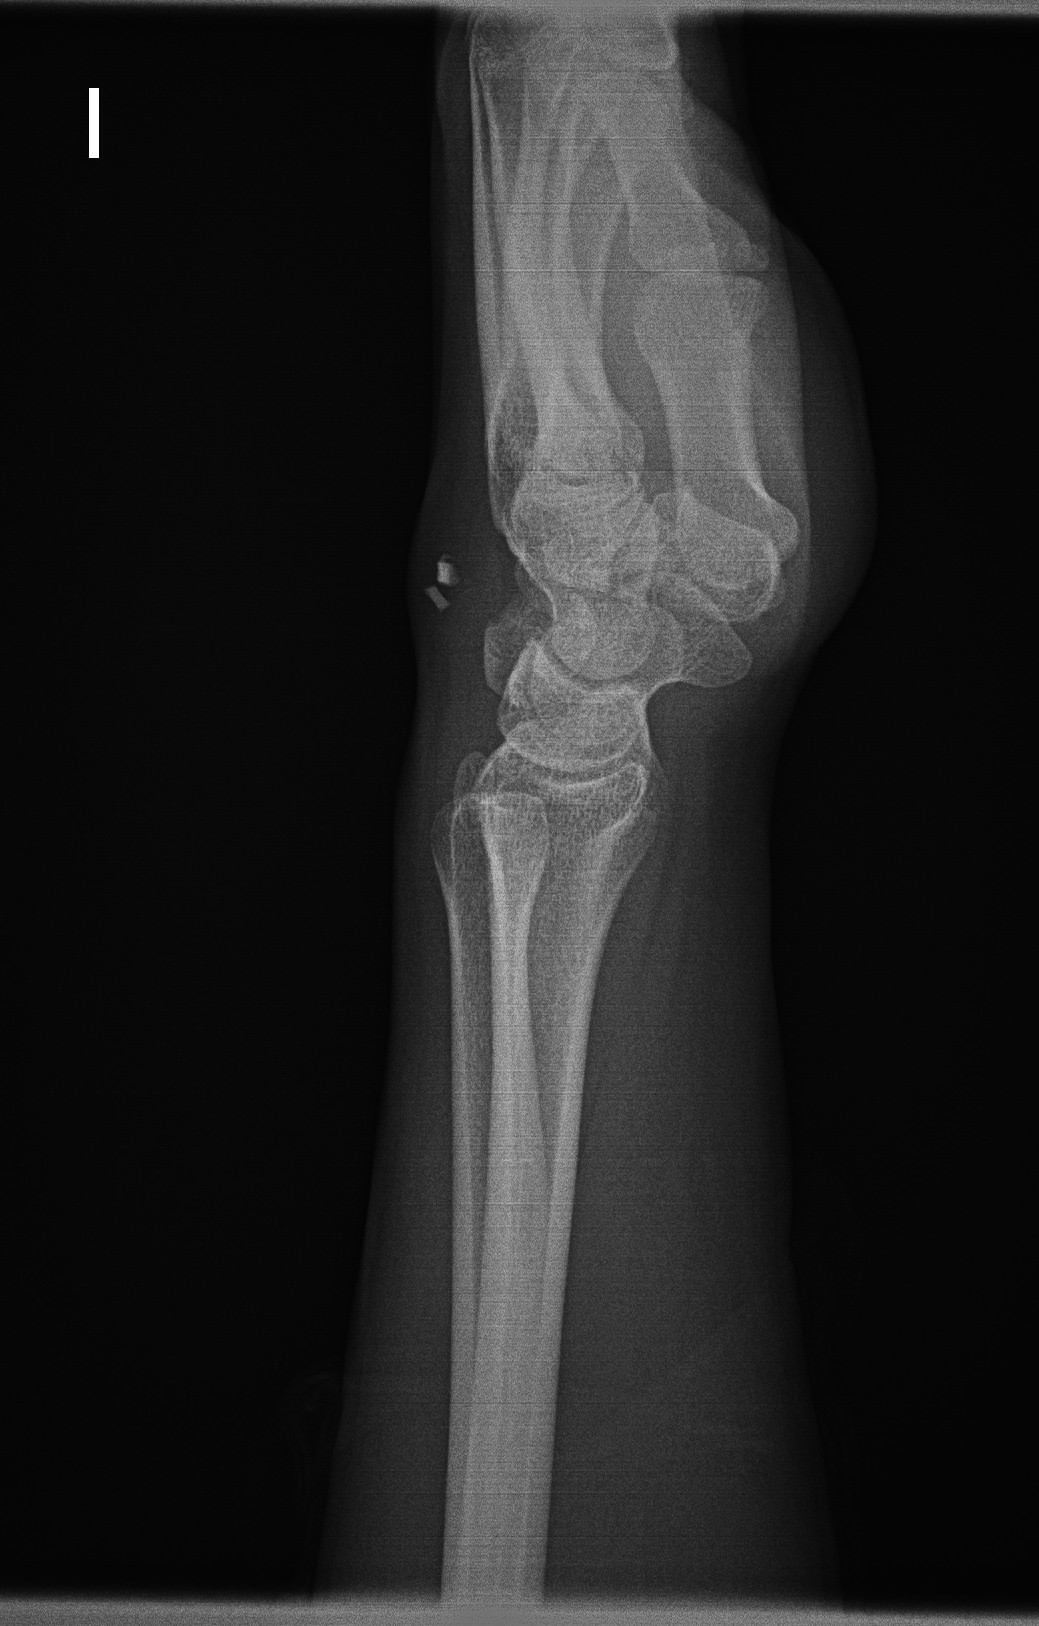

Hombre de 24 años, acude por presentar dolor y tumefacción en el dorso de la mano izquierda de meses de evolución. Refiere traumatismo en dicha mano hace un año con herida y laceración de tejidos blandos. Se le realizó radiografía simple (Rx) que fue interpretada como normal.

Realizamos Rx en la que se observa dos imágenes radiopacas en partes blandas del dorso de la mano.